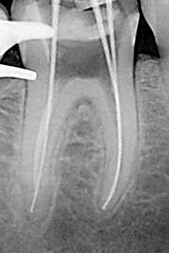

6. Conductometría.

6- Conductometría con RX: consiste en determinar la longitud precisa entre el CDC de cada conducto y el borde incisal o la cara oclusal del diente en tratamiento, considerando como longitud óptima 0,5 a 1mm. del ápice radiográfico AR.

Pasos a tener en cuenta

1.      Se toma una radiografía inicial de diagnóstico ortorradial, con el diente en el centro de la placa, preferiblemente con técnica paralela. Se mide la longitud de todo el diente desde el borde incisal o cúspide oclusal hasta la porción más apical del diente.

2.       Se resta 1 mm. a dicha longitud (distancia existente entre ligamento periodontal y el CDC, no observable en la radiografía). Conocer la longitud promedio del diente es de gran ayuda para determinar la longitud aproximada de trabajo.

3.       Se desplaza el tope de silicona de una lima K 10 ( la elección del calibre de lima debe estar relacionado con el espesor del conducto que muestra la radiografía) y  se aplica la longitud radiográfica a la lima por medio de una regla.

4.      Se introduce la lima en el conducto correspondiente hasta que el tope haga contacto con la referencia anatómica elegida de la corona.

5.      Se toma una radiografía, una vez revelada se verifica la ubicación del instrumento y se hacen los ajustes necesarios, se considera que debe estar ubicada a 0,5 – 1 mm del ápice radiográfico.

6.      Se retira la lima del conducto y nuevamente se mide la distancia entre el tope de goma y la punta del instrumento, esta es la longitud de trabajo definitiva. Se debe anotar en la historia clínica las medidas de cada conducto y el punto de referencia tomado para cada conducto.

7.      Para conductos que se superponen es necesario realizar la técnica de doble incidencia o técnica de Clark, para desproyectar a los conductos vestibulares del palatino o lingual.

Nota: Hoy en día la conductometría por medio de la radiología para determinar la longitud de trabajo,  ha sido complementada para una mejor exactitud, por los localizadores electrónicos de ápices, que tienen como objetivo llegar a límite cemento dentina cemento (CDC)